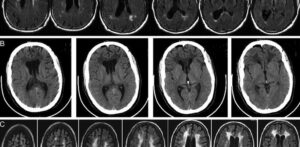

Что такое глиоз головного мозга

Гризмент мозга является вторичным заболеванием, следствием любой из расстройств центральной нервной системы. Ее лечение сложно, и правильно невозможно, потому что замена нервных клеток вспомогательными клетками необратимы. Тем не менее, вы можете остановить перезарядку такой массы или помешать ему. Клиническая картина Центральная нервная система состоит из трех типов клеток: Нейроны — функциональные клетки, которые передают сигналы; …